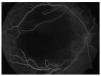

Agudeza visual de percepción de luz, sin localización de la misma en ambos ojos. Segmento anterior sin alteraciones. Presión intraocular en ambos ojos de 16 mmHg por tonometría de Goldmann. Fondo de ambos ojos con vítreo transparente, papilas anaranjadas de características normales, tortuosidad vascular importante, dilatación y arrosariamiento venoso generalizado y zonas de espasmo arteriolar, múltiples hemorragias en flama y en mancha, hemorragias intrarretinianas con centro blanco, hemorragia subhialoidea macular en ojo derecho, lesiones algodonosas peripapilares y áreas poligonales de blanqueamiento retiniano en el polo posterior, con espacios perivasculares respetados (Figuras 1 y 2).

Figura 1. Ojo derecho.